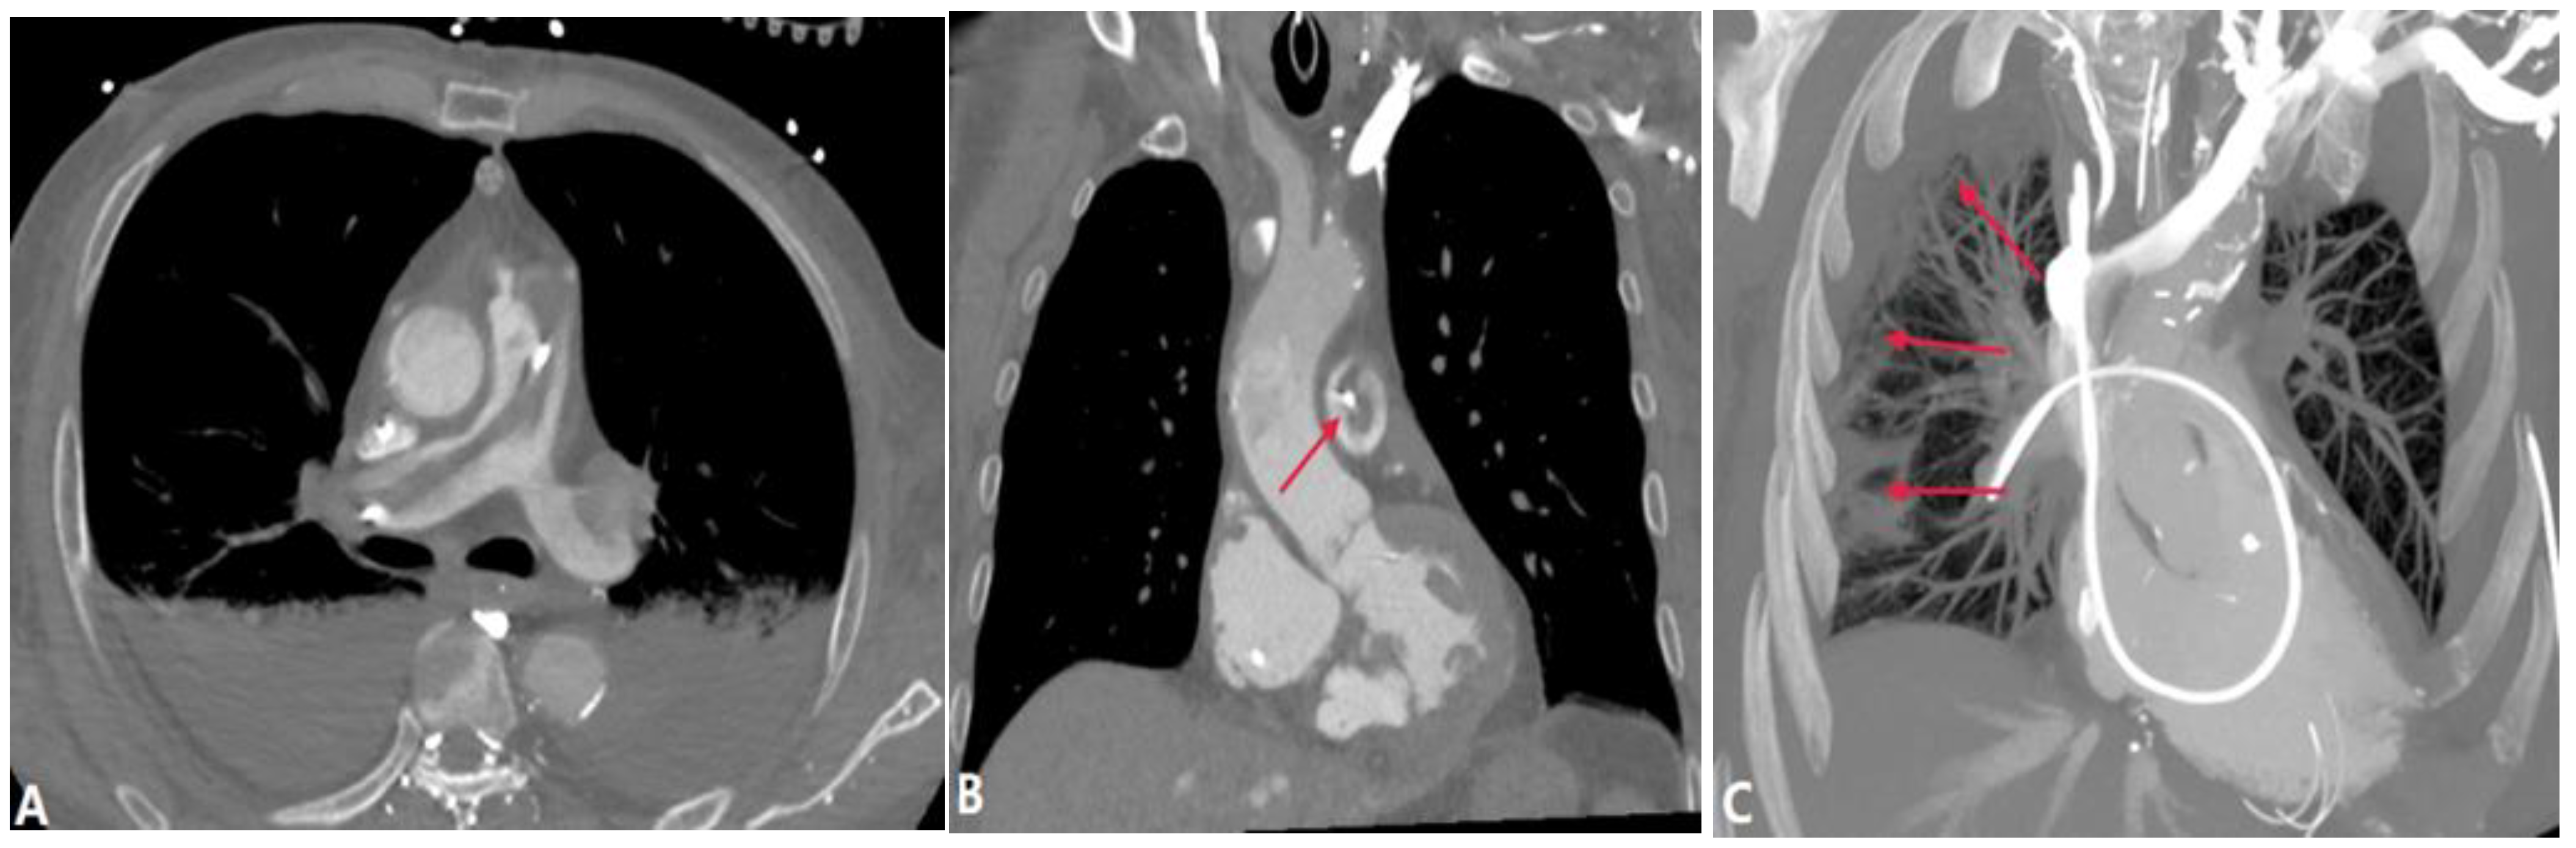

4.3.1. Fibrosis Mediastinitis (FM)

4.3.2. Tumors Causing Pulmonary Artery Stenosis